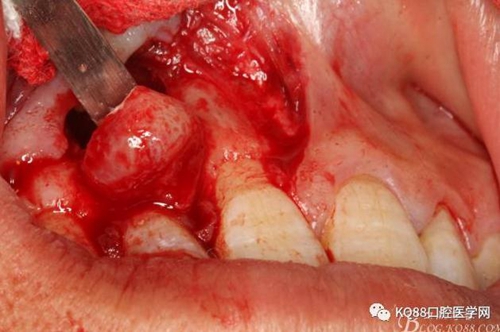

圖8.從垂直切口和水平切口的連接處翻瓣。發(fā)現(xiàn)11和12之間的骨壁有缺損。

圖9.翻開角形瓣后,有骨壁缺損,囊壁有穿孔,這就是溢膿的竇道出口。

圖10。用骨膜剝離器沿著骨壁、緩慢逐漸剝離囊壁。